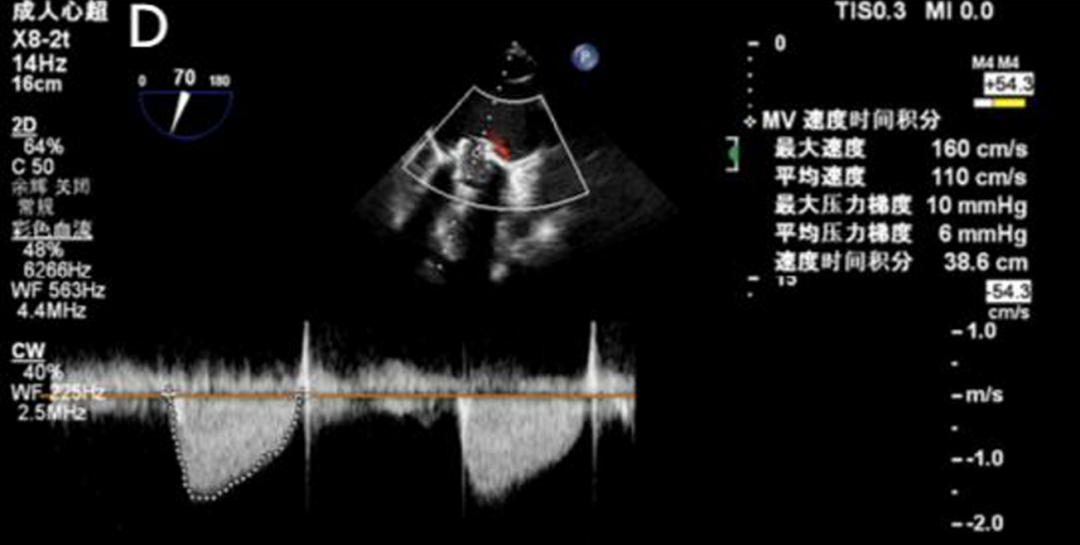

2025年6月4日,在全身麻醉下,通过TEE和荧光镜引导进行手术。通过右颈内静脉建立临时起搏。经左前外侧小切口暴露第五肋间隙,使用双重荷包缝合固定心尖;静脉注射肝素使活化凝血时间(ACT)>250秒。心尖穿刺后,先使用软导丝穿过主动脉瓣口,随后更换为Amplatz超硬导丝(波士顿科学公司)。在快速起搏(180次/分)下,使用18mm球囊对主动脉瓣生物假体进行预扩张。选择21mm ScienCrown瓣膜,旋转手柄将瓣膜从输送系统中逐步释放(视频1)。瓣膜成功植入后,无错位或瓣周漏(PVL)(图2B及视频2)。TEE显示主动脉瓣平均跨瓣压差为6mmHg,无瓣周漏(图2C及D)。随后,使用硬导丝穿过二尖瓣生物瓣进入左心房(视频3)。在快速起搏(180次/分)下于二尖瓣位置植入25mm ScienCrown瓣膜(图2E及视频4)。TEE显示二尖瓣平均跨瓣压差为5mmHg,瓣叶运动正常,无瓣周漏(图2F)。术后荧光检查显示两枚瓣膜均位置良好(图2G)。术后第一天床旁TTE显示二尖瓣压差2.52mmHg,流速0.76m/s;主动脉瓣压差13.39mmHg,流速1.7m/s,提示轻度主动脉瓣狭窄(AS)和正常二尖瓣功能(图3)。患者心功能改善至NYHA II级,并在术后第5天出院。

图2. 使用ScienCrown瓣膜进行经心尖主动脉瓣和二尖瓣ViV手术。A:18mm球囊对主动脉瓣进行预扩张。B:成功植入21mm ScienCrown瓣膜,显示无瓣周漏。C:植入后TEE确认无瓣周漏。D:术后TEE记录主动脉瓣平均跨瓣压差为6mmHg。E:二尖瓣位置25mm ScienCrown瓣膜的理想释放。F:植入后TEE评估显示二尖瓣平均跨瓣压差为5mmHg。G:术后影像学检查显示两枚植入假体瓣膜的位置及形态均正常。